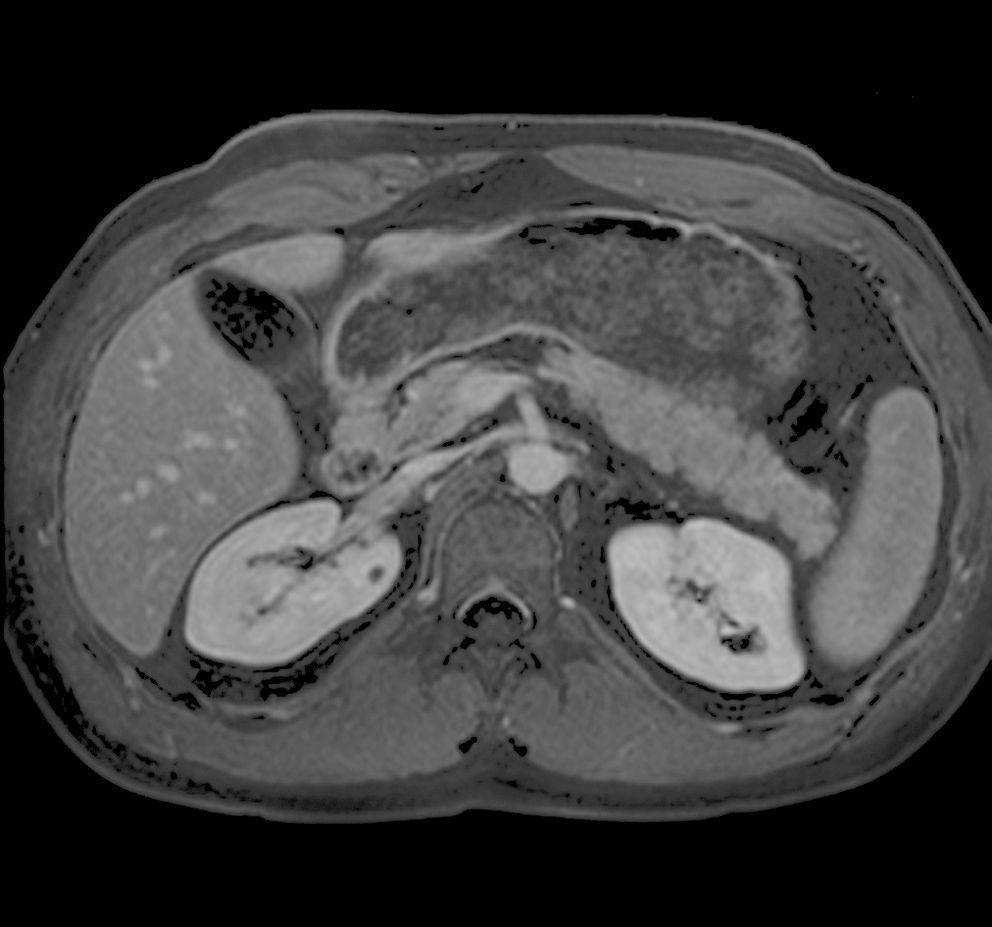

Nieren und Harnwege

Die MRT erlaubt sowohl die Darstellung des Nierengewebes als auch der Harnwege. Besonders bei unklaren Herdbefunde an der Niere kann die MRT oft eine Klärung bringen. Als Nachteil ist die fehlende Darstellung kleiner Nierensteine zu nennen, wenn diese noch nicht in Nierenbecken oder Harnleiter übergetreten sind. Hier ist meist ein einfaches Röntgenbild oder eine Ultraschalluntersuchung vorzuziehen.